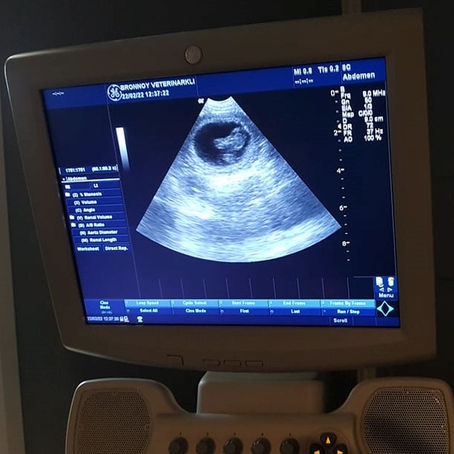

Ona er drektig!

I dag er det gått 30 dager fra Ona først ble parret med Harodalens Kustus II, så da var det dags for ultralydundersøkelse. Den viste at...

22. feb. 2022